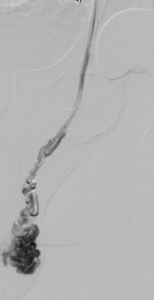

L’embolisation de la varicocèle est réalisée en salle de radiologie interventionnelle. Le patient est allongé sur la table d’examen, et une anesthésie locale est réalisée soit au bras soit à la cuisse pour minimiser l’inconfort. Un petit cathéter est inséré dans une veine, à l’aine ou au bras droits, sous guidage radiologique. Le cathéter est placé à l’aide des rayons X dans la veine testiculaire (en général à gauche si la douleur siège à gauche) et une occlusion est réalisée à l’aide de colle (Glubran 2 par exemple) ou de coïls. La veine dilatée est maintenant occluse et le sang aura un retour non pathologique avec une redirection du flux sanguin. La procédure prend généralement moins d’une heure.